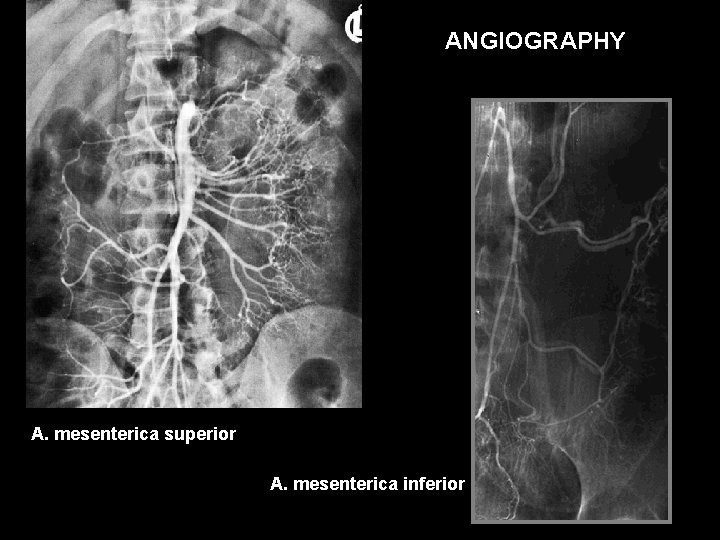

ANGIOGRAPHY A. mesenterica superior A. mesenterica inferior